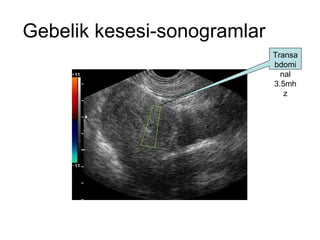

Gebelik kesesi-sonogramlar Transabdominal 3.5mhz

3.5 mhz ile 4-5 haftalık kese

3.5 mhz ile4-5 haftalık kese